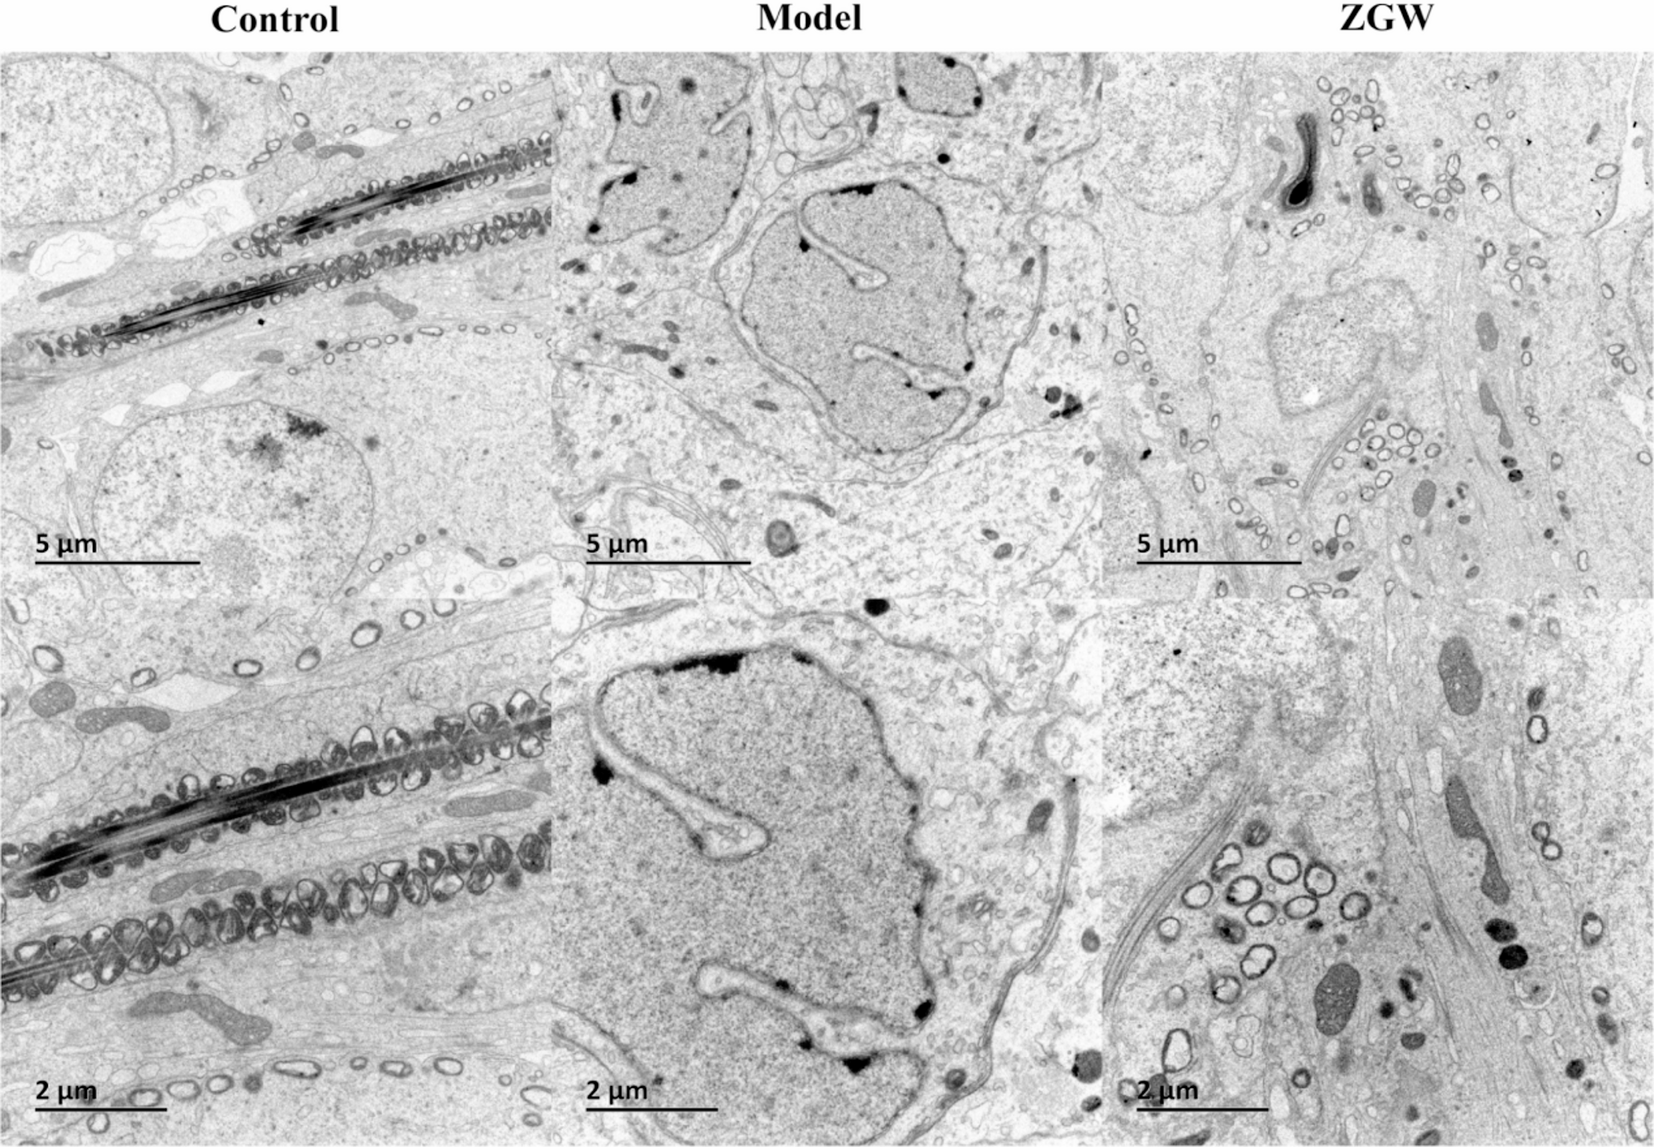

Fig. 9

Comparative analysis of the ultrastructure of rat testicular tissues under Control, Model, and ZGW conditions.In the Control group, spermatocytes at various stages and cellular organelles appear normal, with a large number of sperm.In the Model group, the damage is severe, with swelling of cells and mitochondria, decreased sperm quantity, and the absence of mature sperm.In the ZGW group, the number of sperm and mitochondria is reduced compared to the normal condition.